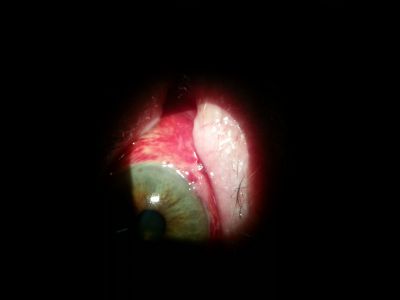

20160318_120826~1.jpg

2012~0.JPG anonFieldLeft.jpg 20160318_120826~1.jpg amniotic_membrane_graft.jpg 383395_10151955171997538_2084480373_n.jpg